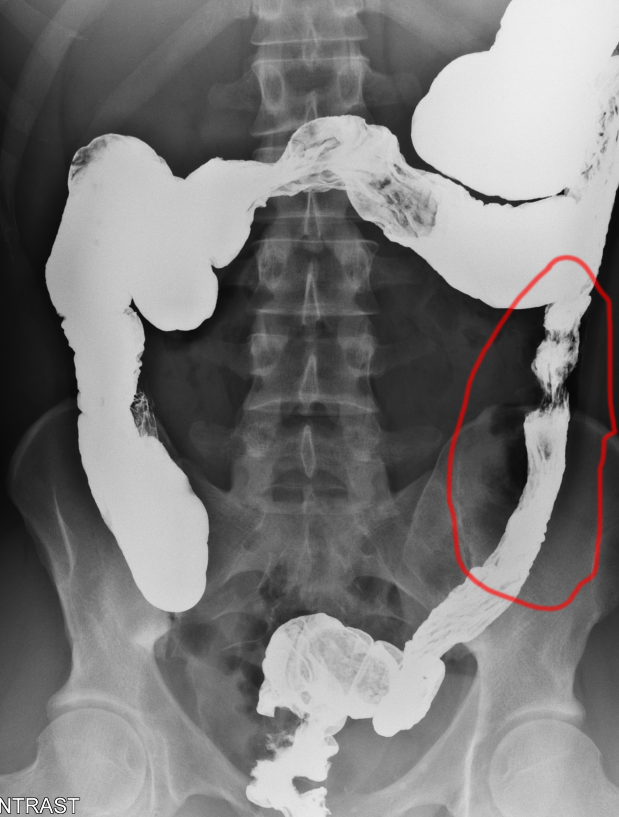

5.5 years ago, I had a major abdominal surgery. Inches of intestine were removed and I was in the hospital for a month trying to train my digestive system to work again.

5.5 years ago, I had a major abdominal surgery. Inches of intestine were removed and I was in the hospital for a month trying to train my digestive system to work again.

Three kicks. Three brutal toe kicks. Directly into the area of the surgery.

Three kicks. Three brutal toe kicks. Directly into the area of the surgery.

I don& #39;t remember the pain. I remember the disgusting feeling of my descending colon shifting and collapsing.

Around 4 months after the surgery, I regained slight feeling in the area. Feint, reactionary movements which had to be manipulated to get the digestive process rolling.

Around 4 months after the surgery, I regained slight feeling in the area. Feint, reactionary movements which had to be manipulated to get the digestive process rolling.

Those kicks did not cause shocking pain. I felt something inside me shut off. Those feint peristaltic movements were gone. The polite static energy I was growing in my pelvic floor was gone. It still is.

Half of my pelvis is dead, and I have to use a machine to get food through.

Half of my pelvis is dead, and I have to use a machine to get food through.

My health situation& #39;s been complicated from birth. The surgeries I& #39;ve had are battles to get through and heal from every time, & 2014 was the hardest one.

My health situation& #39;s been complicated from birth. The surgeries I& #39;ve had are battles to get through and heal from every time, & 2014 was the hardest one.

I didn& #39;t have health insurance at the time. I was in the ER three weeks after the assault, in a pain-filled panic, desperately concerned about another septic obstruction.

I didn& #39;t have health insurance at the time. I was in the ER three weeks after the assault, in a pain-filled panic, desperately concerned about another septic obstruction.